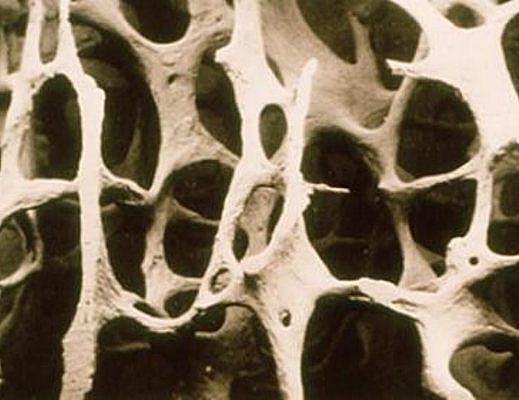

Il tema è importante: superati i 50 anni una donna su tre comincia ad avere le ossa più fragili.

“L’Azienda Ospedaliera Universitaria è attenta alla salute delle donna – spiega il direttore generale Elvira Lenzi - Iniziative come queste sono davvero preziose per ricordare alla popolazione femminile l’importanza della prevenzione e dei controlli periodici, perché l’osteoporosi è un problema ad ampia diffusione. La prevenzione dovrebbe iniziare fin dalla giovane età con stili di vita appropriati, attività fisica adeguata e alimentazione corretta. La salute delle ossa non deve essere mai trascurata: l’osteoporosi è una malattia tipicamente femminile e "silenziosa. I nostri Ospedali, già certificati con i Bollini Rosa, dimostrano ancora una volta la massima sensibilità ai percorsi di prevenzione e cura delle patologie del mondo femminile. Per questo vogliamo sensibilizzare la popolazione ed avvicinarla sempre più alla cultura della salute in tutte le fasce d’età. Di qui l’importanza di dedicare un particolare momento di attenzione alla salute delle ossa delle donne salernitane che, oltre ad usufruire di consulenze gratuite potranno partecipare ad incontri di approfondimento che hanno l’obiettivo di offrire risposte adeguate ad una patologia da non sottovalutare”.